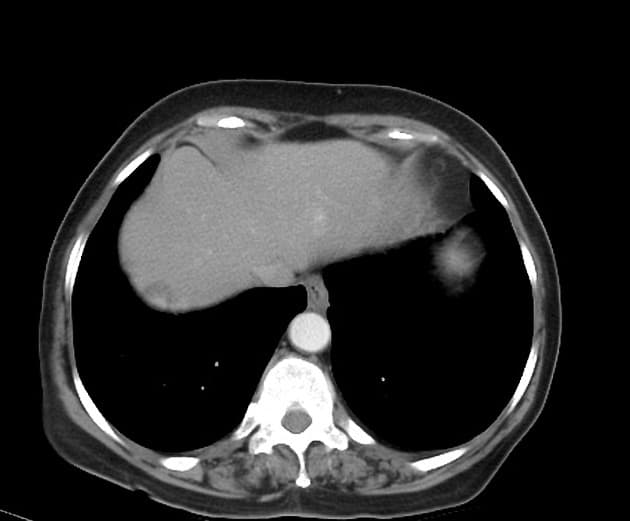

Axial T1 C+ fat sat

- Nhiều tổn thương khối mờ tăng quang khuếch tán khắp gan trên thì tĩnh mạch cửa.

- Các khối này tăng tín hiệu nhẹ trên T1 và T2, ranh giới không rõ trên hình ảnh thông thường sau tiêm thuốc cản quang, nhưng hiện rõ là nhiều tổn thương giảm tín hiệu trên chụp chậm với Primovist (chỉ điểm không có tế bào gan, do đó loại trừ u tăng sản khu trú - FNH).

- Gan nhiễm mỡ, giảm tín hiệu trên pha out-phase.

Nhiều tổn thương khối tăng quang, không có tế bào gan dựa trên hình ảnh chụp chậm sau tiêm thuốc cản quang. Chẩn đoán phân biệt bao gồm: bệnh di căn, ung thư biểu mô tế bào gan đa ổ (HCC) và u tuyến gan. Bệnh nhân đã được sinh thiết 3 tổn thương riêng biệt, kết quả đều cho thấy u tuyến gan (adenoma). Vì có trên 10 tổn thương, nên được gọi là tăng sản tuyến gan (adenomatosis). Tình trạng này có thể liên quan đến việc sử dụng thuốc tránh thai uống (OCP). Không thấy hình ảnh xuất huyết cấp, một biến chứng có thể xảy ra trong bệnh lý này.

Tăng sản tuyến gan (Hepatic adenomatosis)